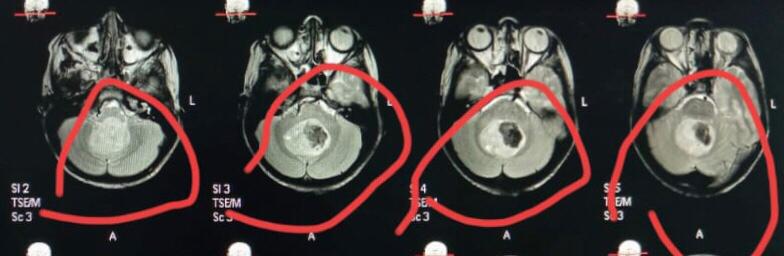

وأضاف الدكتور أحمد كمال مدير مستشفى الجراحات المتخصصة جامعة سوهاج، أنه بعد عمل أشعة الرنين المغناطيسي تبين وجود ورم خبيث بالفص الخلفي من المخ ضاغط على المخيخ وجزع المخ، لافتًا إلى أن هذه الحالات تعتبر من أخطر حالات أورام المخ وقاع الجمجمة لما يحمله الجزء المصاب به الورم من مراكز حساسة.

وأكد الدكتور عابدين خيرالله قاسم رئيس قسم جراحة المخ والأعصاب جامعة سوهاج، أن الفريق الطبي الجراحي نجح في استئصال الورم كليًا مع الحفاظ على المراكز والشرايين المحيطة بالورم للحفاظ على المخيخ وجذع المخ، اعقبها نقل المريض إلى العناية المركزة للأطفال لإفاقة الطفل تدريجيًا، وبعد مرور يوم كامل للإفاقة استعاد الطفل الوعي كاملًا مع حركة الأطراف طبيعيًا.